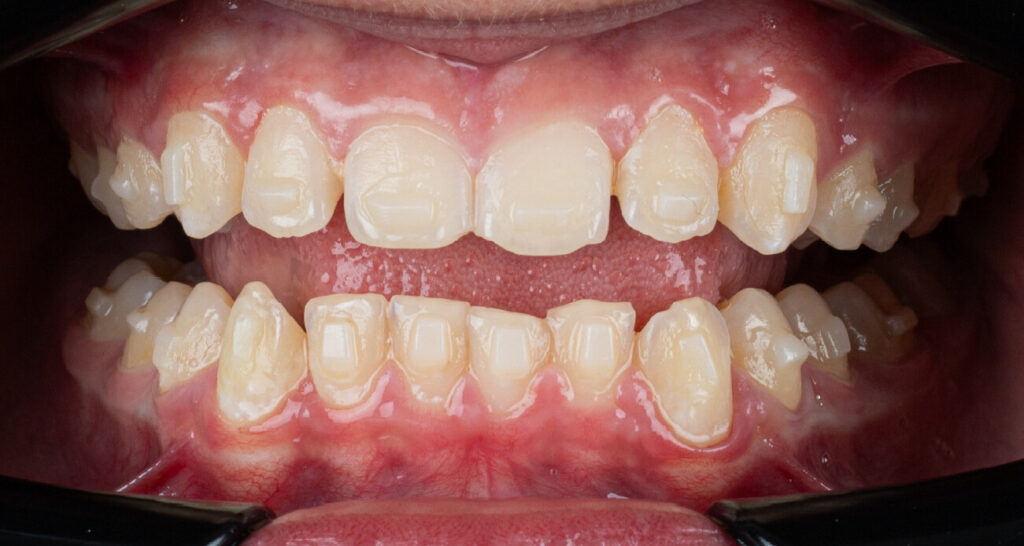

Um paciente do sexo masculino, com 13 anos de idade, apresentou-se com uma mordida profunda, caracterizada pela cobertura quase completa dos incisivos mandibulares. A avaliação clínica revelou apinhamento em ambas as arcadas, rotações dentárias e proclinação dos incisivos laterais superiores, contribuindo para as preocupações estéticas do paciente. O perfil facial era retrusivo, consistente com retrognatismo mandibular, e não foram detectadas anomalias periodontais significativas.

O paciente apresentava uma relação esquelética de Classe II com molares e caninos bilaterais em Classe II e um padrão dentário de Classe II divisão 2. A mordida profunda estava associada a um apinhamento anteroinferior e a uma curva de Spee acentuada. A análise facial revelou boa simetria, um terço facial inferior ligeiramente aumentado e um perfil convexo caracterizado por retrusão mandibular e do mento. A competência labial estava ligeiramente reduzida, com diminuição do ângulo nasolabial e leve tensão do músculo mentoniano, fatores que comprometiam a harmonia facial global.